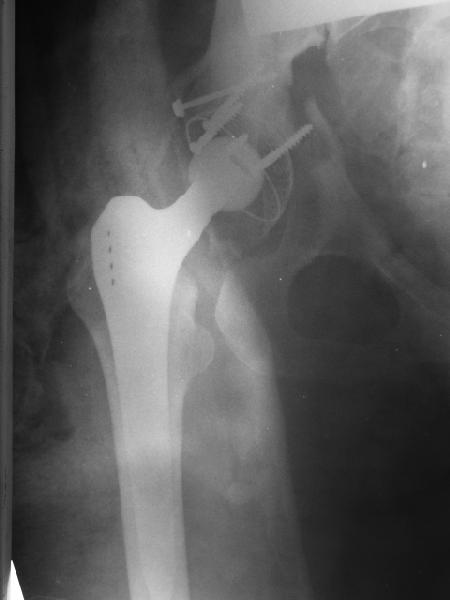

Обратились коллеги из городской больницы N36. Женщине 39 лет по поводу диспластического коксартроза около года назад выполнено эндопротезирование правого тазобедренного сустава. Вчера ехала на госпитализацию на протезирование второго сустава, и попала в аварию.

Получила поперечный перелом правой вертлужной впадины (снимок прилагается) с переломом ветвей лонной кости на другой стороне (inletview также в приложении), а также поперечный перелом дистального метафиза бедра на этой же стороне. Что посоветуете в отношении протеза и впадины? Спасибо заранее.

A colleague of mine from another hospital requests opinion. A female 39 years old was operated ~1 year ago - right side THA for hypoplastic hip. Yesterday she was going to the hospital for THA ofthe second hip but got involved in a car accident.She admitted with right acetabular and left rami fractures (images attached). Also trasverse fracture of the right distal femur.Seeking your advice regarding the acetabular fracture. THX!

Ножка Алтимед, а чашка цементая???? Хороший гибрид. Насколько позволяет рентгенограмма, можно судить, что чашка стабильна (за счет цемента и арматуры в виде винтов). Нужен постельный режим не менее 6 недель.

Ситуация редкая и нестандартная. Складывается впечатление, что эндопротез вертлужной впадины стабилен. Я бы выполнил остеосинтез перелома в/впадины реконструктивной пластиной. Эти переломы срастаются хорошо.

Больная оперирована мной по поводу диспластического коксартроза 5-6 месяцев назад.

Установлена RM-чашка бесцементная,ножка тип Цвайммюллер производства Мathys,сделана костная пластика.В настоящее время необходим остеосинтез реконструктивной пластиной без удаления чашки,так как чашка стабильна.